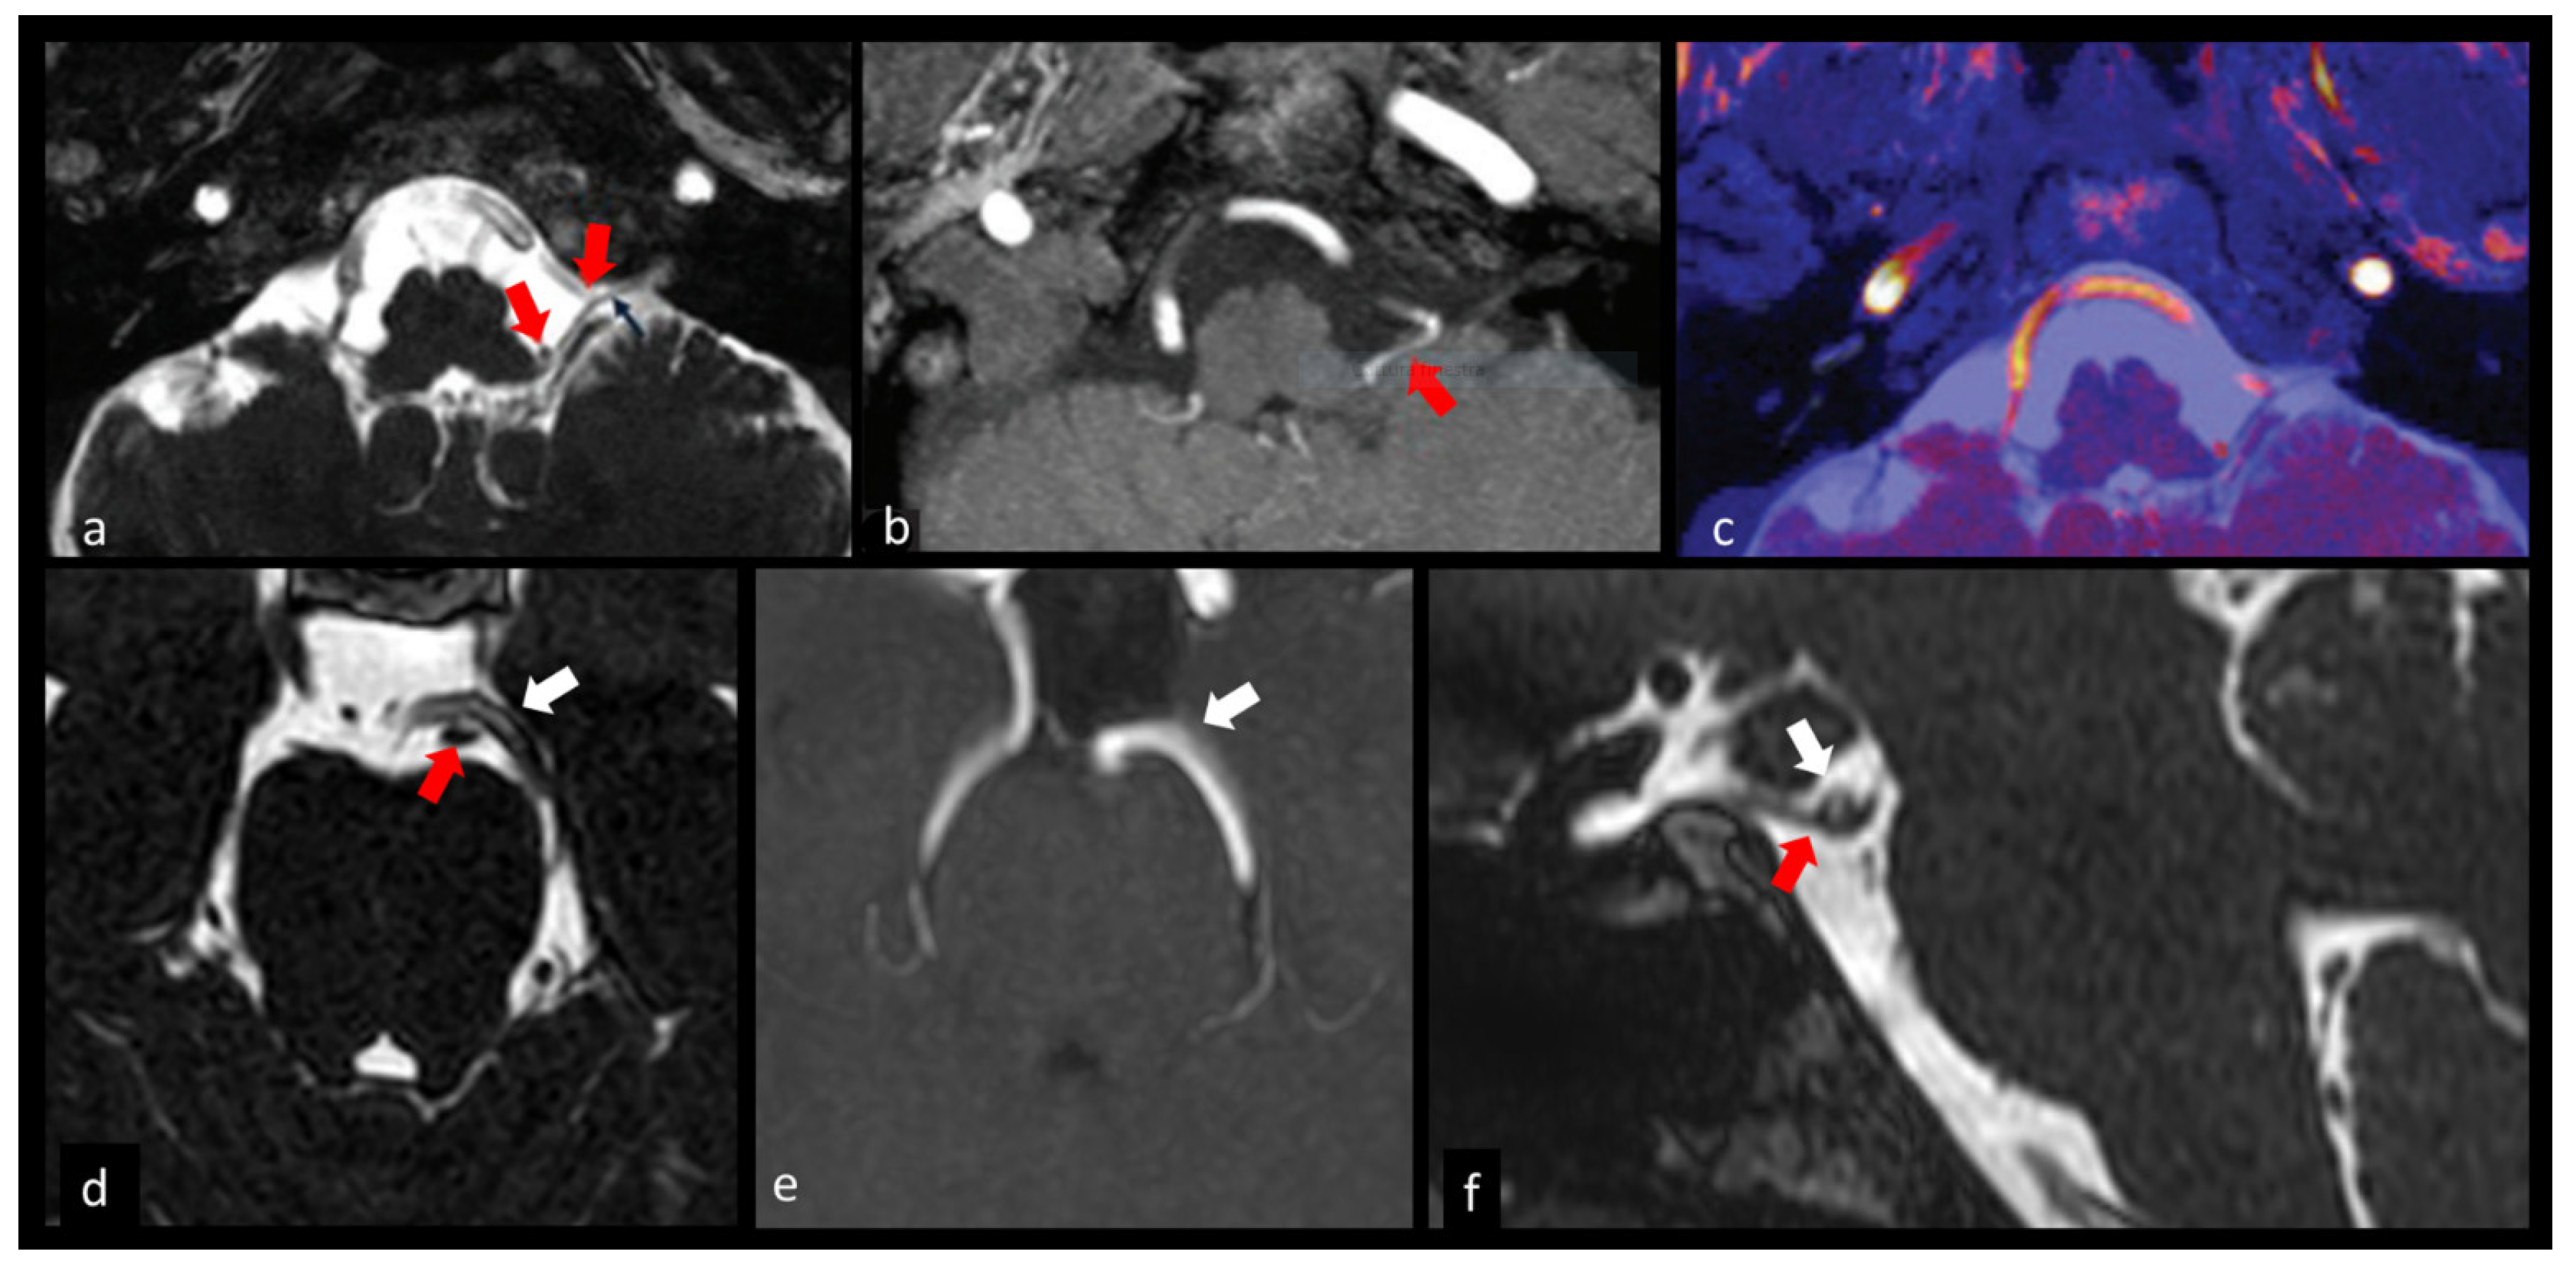

- Jia, J.M.; Guo, H.; Huo, W.J.; Hu, S.W.; He, F.; Sun, X.D.; Lin, G.J. Preoperative Evaluation of Patients with Hemifacial Spasm by Three-dimensional Time-of-Flight (3D-TOF) and Three-dimensional Constructive Interference in Steady State (3D-CISS) Sequence. Clin. Neuroradiol. 2016, 26, 431–438. [Google Scholar] [CrossRef] [PubMed]

- Granata, F.; Vinci, S.L.; Longo, M.; Bernava, G.; Caffo, M.; Cutugno, M.; Morabito, R.; Salamone, I.; Tomasello, F.; Alafaci, C. Advanced virtual magnetic resonance imaging (MRI) techniques in neurovascular conflict: Bidimensional image fusion and virtual cisternography. Radiol. Med. 2013, 118, 1045–1054. [Google Scholar] [CrossRef] [PubMed]

- Mittal, P.; Mittal, G. Painful tic convulsif syndrome due to vertebrobasilar dolichoectasia. J. Neurosci. Rural Pract. 2011, 2, 71–73. [Google Scholar] [CrossRef] [PubMed]